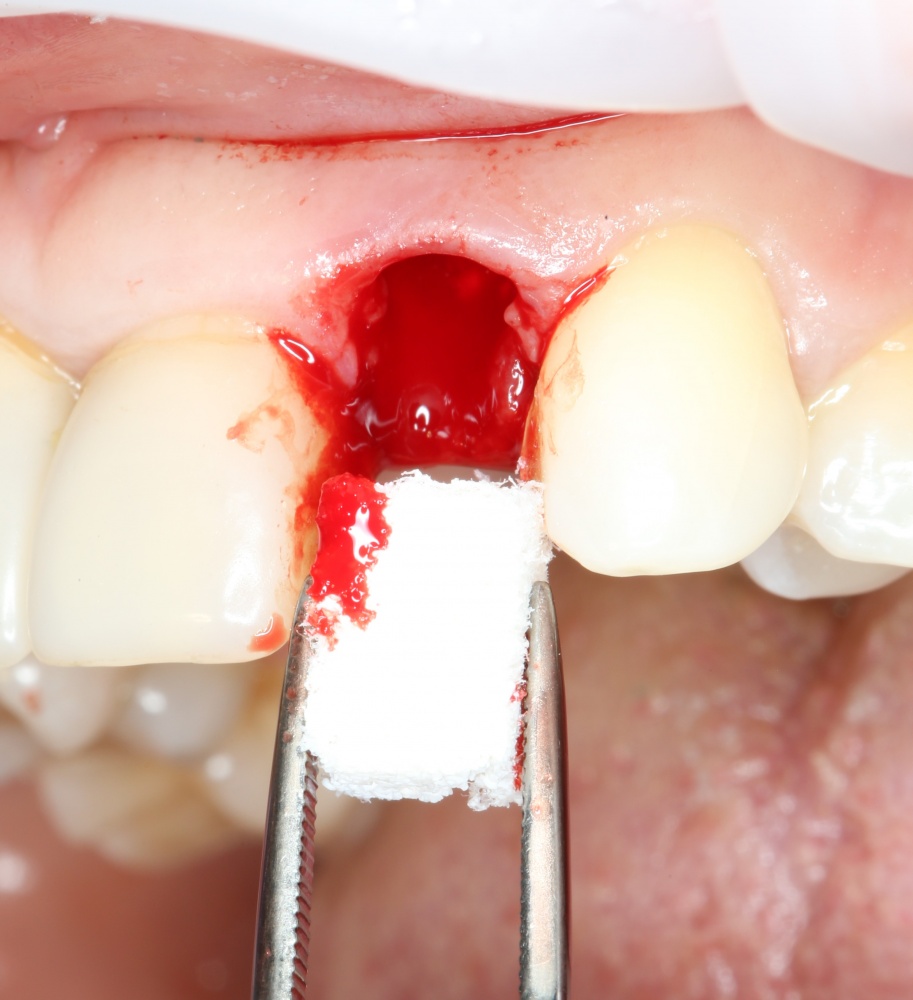

Изоляция области аутографта и имплантатов барьерной мембраной.

Конкретно в этом клиническом случае между костным аутотрансплантатом, ложем и имплантатами есть пустое пространство. Если его не изолировать от мягких тканей, они прорастут и осложнят интеграцию аутографта. Поэтому я решил перекрыть костный блок барьерной мембраной, пусть это делает хирургическую операцию немного дороже.

— много лет мы используем антибиотики для интраоперационной профилактики инфекционно-воспалительных осложнений. Уже в то время мы пришли к выводу, что удобнее всего — порошки антибактериальных препаратов для приготовления раствором: дешевые, стерильные, в удобной упаковке. Прямо в виде порошка их можно добавлять в графт, растворы для ирригации, либо использовать так, как показано на фото. Еще мы используем порошок антибиотика для изготовления пасты, которой обрабатываем имплантаты в процессе ревизии или при лечении периимплантита. Это удобнее и эффективнее, чем интраоперационное использование жидких форм антибактериальных препаратов.